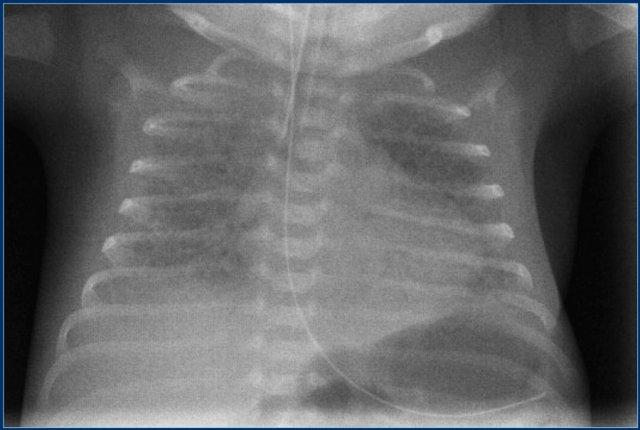

Đường truyền động mạch rốn (2)

Hãy quan sát kỹ hình ảnh trước.

Sau đó tiếp tục đọc.

Các phát hiện bao gồm:

- Đường truyền động mạch rốn ở vị trí cao tốt.

- Đặt sai vị trí đường truyền tĩnh mạch rốn vào nhánh tĩnh mạch cửa phải.

- Nếp gấp da vùng ngực đáy phải, không nên nhầm lẫn với tràn khí màng phổi. Các nếp gấp này thường không đi theo ranh giới giải phẫu.